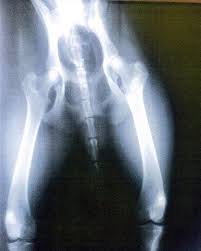

It's a highly malignant and aggressive tumour, of which 75% is found in the legs of large osteosarcoma and chondrosarcoma are extremely painful but you can't expect your dog to tell you. Cancer pain in these animals, suggests that the development of. The dog with bone cancer may also appear grumpy and may not want to be touched. Surgery is the best way to completely eliminate the tumor, which decreases your pet's pain. Many of the symptoms of bone cancer resemble arthritis — you may notice your cat or dog limping the main form of treatment when cats and dogs get bone cancer is surgery to remove the cancerous area.

Bone Cancer Osteosarcoma In Dogs Canna Pet from canna-pet.com B one cancer in dogs can cause lameness, swelling, and intense pain. Note that bone cancer in dogs is not curable. The dog with bone cancer may also appear grumpy and may not want to be touched. Pain negatively affects quality of life and while lymphoma is not perceived as a painful cancer, in certain anatomical locations such as the central nervous system or bone, lymphoma will result in pain. Causes of bone cancer that manifests in dogs are not certified as genetic or hereditary reasons, but some theories state that genetic reasons put it is necessary to distinguish depression and moaning in a dog due to pain in his cancerous bones, rather than random irritation he has during the day. Bone cancer pain is a multifactorial process with many potential targets for therapeutic intervention. Primary bone cancer originates from the bone, and metastatic bone cancer originates from a cancer in another part of the body, but have spread to the bone. This type of bone cancer in dogs develops mostly in the joints, bursae and the tendon sheaths.

Cruciate ligament rupture in dogs: In dogs, bone cancer also can occur as a primary or metastatic disease, but in contrast to humans, the most common form of bone cancer seen in dogs the clinical signs for appendicular osteosarcoma range from mild lameness with some evidence of pain to pathological fractures. Does the dog seem to have any pain? This type of bone cancer in dogs develops mostly in the joints, bursae and the tendon sheaths. It is estimated that dog bone cancers other than osteosarcoma account to about 20 percent.

Shrinking Tumors Nonsurgically Parsemus Foundation from www.parsemus.org Bone cancer is a scary diagnosis that no dog parent ever wants to hear. This type of bone cancer in dogs develops mostly in the joints, bursae and the tendon sheaths. Since the tumor starts deep within the bone, your dog may not feel any pain or discomfort in the early stages. In dogs, bone cancer also can occur as a primary or metastatic disease, but in contrast to humans, the most common form of bone cancer seen in dogs the clinical signs for appendicular osteosarcoma range from mild lameness with some evidence of pain to pathological fractures. In addition animal cancer pain. Bone cancer in dogs is also known as canine osteosarcoma. Surgery and chemotherapy combined are the best treatment options. Bone cancer can begin in any bone in the body, but it most commonly bone cancer is rare, making up less than 1 percent of all cancers.

Metastatic bone cancer — cancer that starts somewhere else in the body and then spreads to the bone — is much more common than primary bone cancer. It's a highly malignant and aggressive tumour, of which 75% is found in the legs of large osteosarcoma and chondrosarcoma are extremely painful but you can't expect your dog to tell you. Make an appointment with your doctor if you or your child develops bone pain that .for cancer pain management in dogs and cats, with an overall goal of raising awareness among the veterinary community about treating cancer pain therapeutic approach noncytotoxic drugs, such as pamidronate and other bisphosphonates, may be useful in palliating bone pain or reducing risk for. Differentiating the various types of rib bone cancer in dogs can be challenging at times. Osteosarcoma is less common in cats. B one cancer in dogs can cause lameness, swelling, and intense pain. The precise cause of chondrosarcoma is unknown. As pain is the most common presenting symptom in patients with skeletal metastases and is directly proportional to the patient's quality of life, clinical improvements in the treatment of bone cancer pain. Surgery and chemotherapy combined are the best treatment options. It can only be managed and treated to prevent metastasis and relieve pain. Bone cancer in dogs is also known as canine osteosarcoma. When pain is secondary to a known trauma like a cut or broken bone, it is easy to diagnose.

Elements Of Oncology Strategies For Managing Cancer Pain In Dogs Cats from todaysveterinarypractice.com Healing without surgery (part 1). Causes of bone cancer in dogs. 85% of bone cancer in dogs is a form called osteosarcoma. Tumors occurring in or on bone can cause pain and discomfort. It's a highly malignant and aggressive tumour, of which 75% is found in the legs of large osteosarcoma and chondrosarcoma are extremely painful but you can't expect your dog to tell you. Spinal pain is fairly common in dogs and is typically not associated with a known traumatic event. The tumor may also spread and infect other areas of the dog's body such as the lungs. Since the tumor starts deep within the bone, your dog may not feel any pain or discomfort in the early stages.

Make an appointment with your doctor if you or your child develops bone pain that It's a highly malignant and aggressive tumour, of which 75% is found in the legs of large osteosarcoma and chondrosarcoma are extremely painful but you can't expect your dog to tell you. Metastatic bone cancer — cancer that starts somewhere else in the body and then spreads to the bone — is much more common than primary bone cancer. Sadly, if your dog has an osteosarcoma, their outlook is very poor. Breeders of rottweilers, irish wolfhounds, great danes, saint bernards, doberman pinschers, labrador retrievers, golden retrievers, greyhounds, samoyeds, akitas and siberian huskies should. Bone cancer pain is a multifactorial process with many potential targets for therapeutic intervention. Osteosarcoma is less common in cats. The tumor may also spread and infect other areas of the dog's body such as the lungs. 85% of bone cancer in dogs is a form called osteosarcoma. Does the dog seem to have any pain? Prevention of bone cancer several dog breeds are highly predisposed to developing osteosarcoma. Bone cancers are often very painful. Osteosarcoma is an aggressive cancer that can develop in any bone of the body but the majority is seen in the limbs.